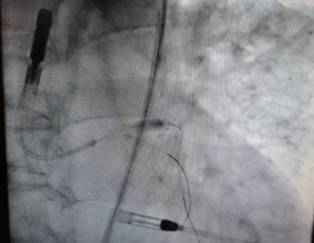

术中置入CorVad左心室辅助装置,针对左主干、前降支重度钙化病变行旋磨,在IVUS指导下成功行冠脉左主干分叉病变血运重建。手术过程中患者生命体征平稳,在导管室技师及护理团队的通力合作下,手术获得圆满成功。